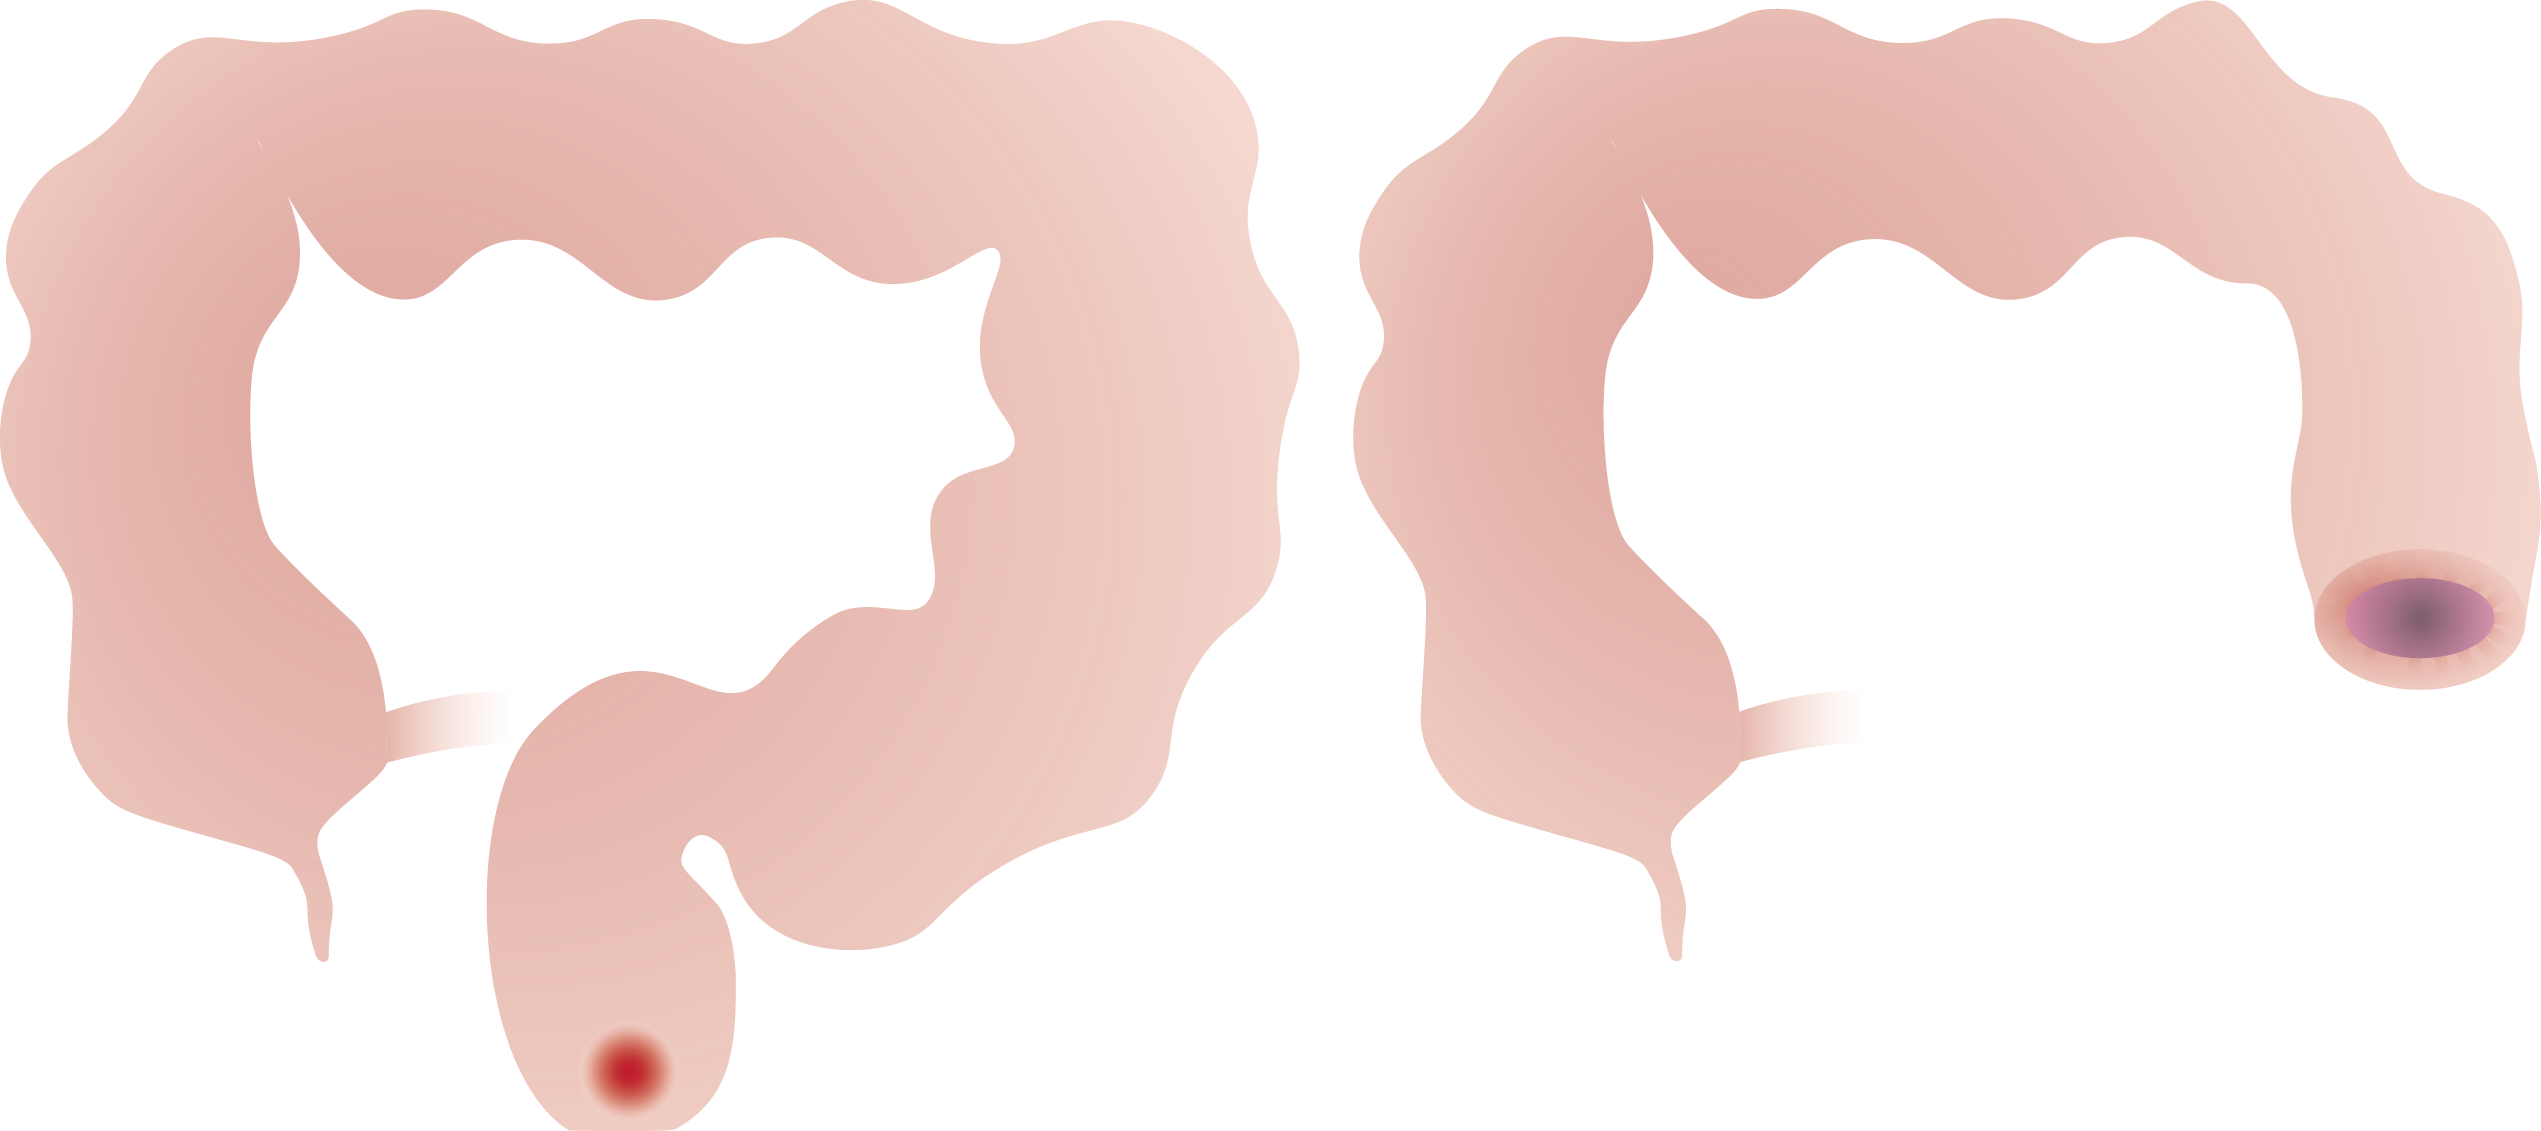

Dikkedarmkanker, ook wel colonkanker of coloncarcinoom genoemd, is een veelvoorkomende en potentieel levensbedreigende aandoening die ontstaat in de dikke darm, het laatste deel van het spijsverteringsstelsel. Deze vorm van kanker ontstaat doorgaans uit een ongecontroleerde groei van slijmvlies tot poliepen die, indien onbehandeld, verder kunnen uitgroeien tot kwaadaardige tumoren.

Bij een operatie voor darmkanker verwijdert de chirurg behalve de tumor aan beide kanten van de tumor ook een stukje gezond weefsel en een deel van het vet met lymfeklieren vlak bij de tumor. Deze lymfeklieren worden nadien onderzocht onder de microscoop. Afhankelijk van de uitslag bepaalt de arts of er een reden is om aanvullend chemotherapie te adviseren.

Afhankelijk van de locatie van de tumor moet dus een ander stukje van de dikke darm en zijn bloedvoorziening worden mee weggenomen.

Naargelang de plaats van de aandoening spreekt men van een:

• Linker hemicolectomie (colectomie = verwijderen van dikke darm, hemi = half) en sigmoidectomie (wegnemen van het voorlaatste deel van de dikke darm).

• Rechter hemicolectomie (colectomie = verwijderen van dikke darm, hemi = half).

• Rectum resectie (= verwijderen van de endeldarm zonder de anus).

• Rectumamputatie (= verwijderen van de endeldarm met de anus).

• Totale colectomie (= verwijderen van de hele dikke darm met eventueel dunne darm 'pouch').